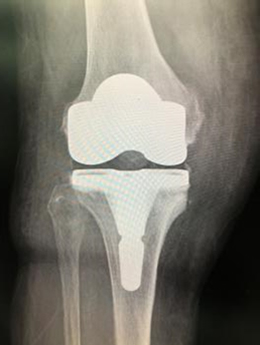

【人工膝関節】

- 術前

- 術後